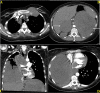

Nonmelanoma skin cancer is the most common cancer in the world, and lung cancer is the leading cause of death from cancer. Histologically, squamous cell carcinoma (SCC) is the second most prevalent type of both skin and lung cancers. We report the case of a 38-year-old female with metastatic, poorly differentiated lung SCC detected on chest X-ray after she presented to the hospital with cough and dyspnea. She had had a 7.5 cm moderately differentiated well-circumscribed posterior scalp SCC completely excised eight years earlier. CT scan showed a large right lung mass, nodular filling defect in the left atrium (LA), and metastases to the adrenal glands and the first rib. Her pulmonary tumor extends to the LA via the right superior pulmonary vein, which is rarely reported in the literature. Ultrasound-guided biopsy of the rib mass showed poorly differentiated SCC. The patient received urgent radiotherapy, given superior vena cava and mainstem bronchus compression. Head CT showed no brain metastasis. A biopsy of the left adrenal initially reported an undifferentiated pleomorphic sarcoma; however, a second pathologist reported it as a poorly differentiated carcinoma of lung origin. At least three pathologists verified the specimen, and it had a PD-L1 test with a 1-49% score. An initial echocardiogram confirmed the LA mass. The patient received a Paclitaxel-Carboplatin-Pembrolizumab regimen as the first-line treatment for metastatic SCC. A repeat echocardiogram after cycle 1 showed a decrease in the size of the tumor in the LA. Almost five months after her initial visit, this young woman's symptoms and performance status have improved post-palliative radiotherapy and chemo-immunotherapy. Follow-up CT showed smaller lung, nodal, adrenal, and costochondral masses, and evidence of necrosis. This case is clinically relevant because it represents a common problem presenting uncommonly. Moreover, it highlights that ultrasound-guided interventions and medical imaging are essential in directing metastatic cancer diagnosis, treatment, and follow-up, especially when pathology cannot confirm but only presume a specific diagnosis.